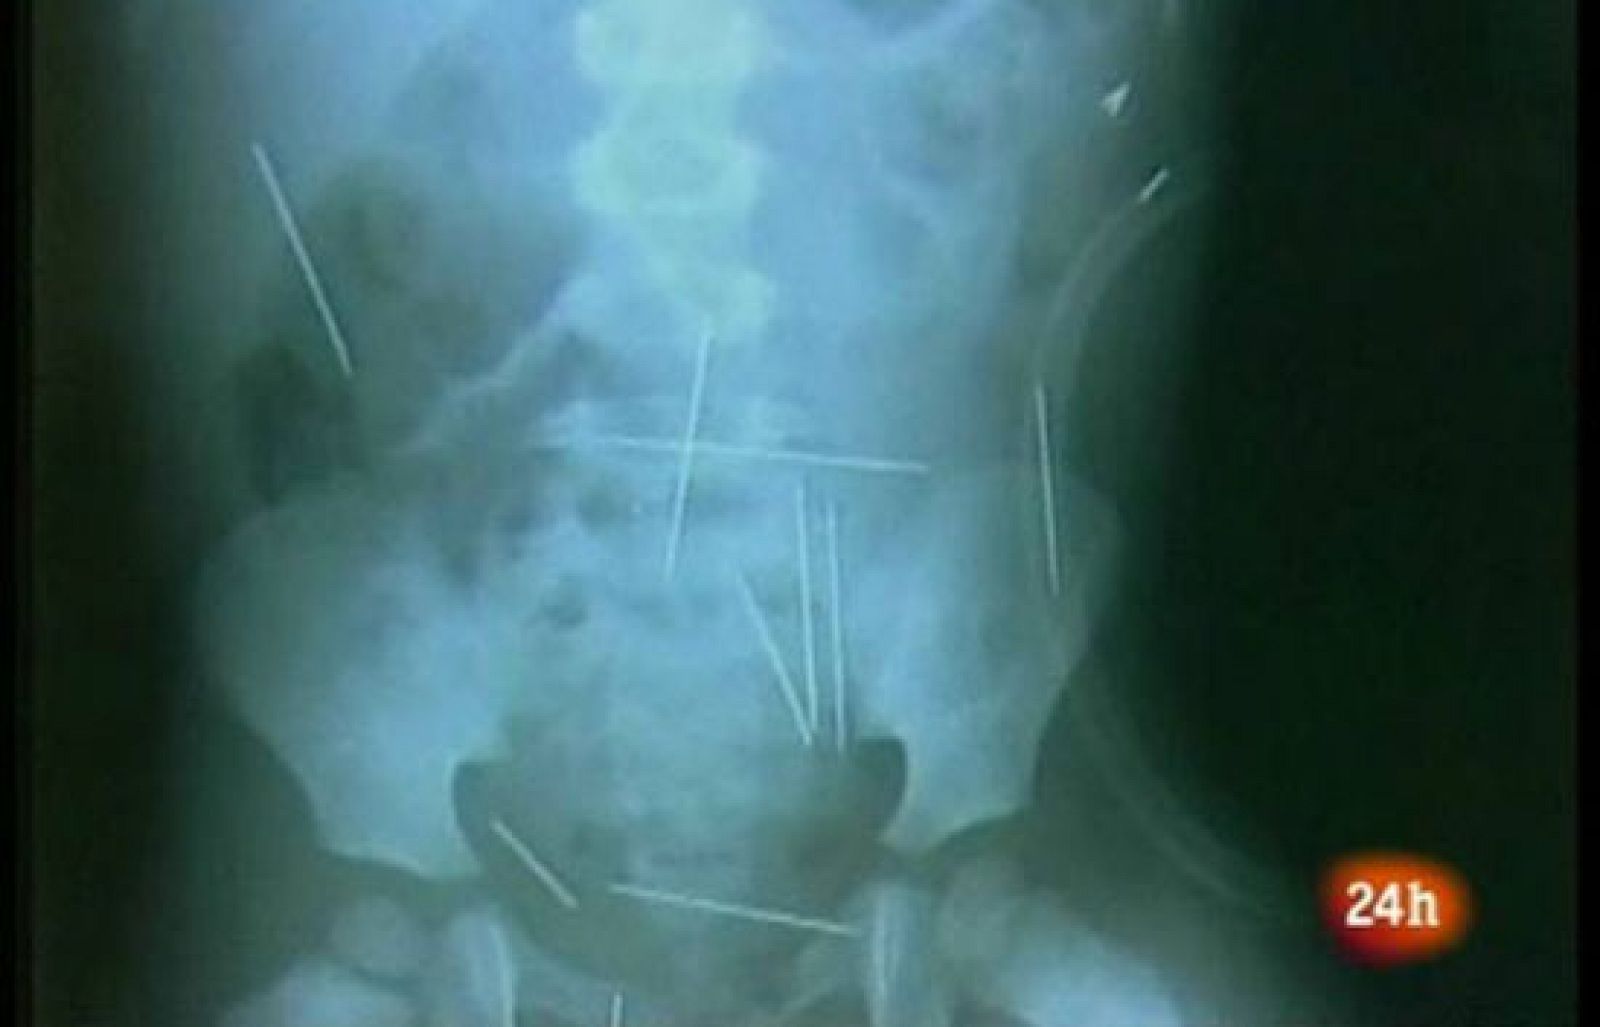

El padrastro de un niño de dos años que fue internado de gravedad en el estado de Bahía, Noreste con unas 40 agujas en el cuerpo, ha admitido haber clavado los objetos durante rituales de magia negra, informó la policía brasileña.

El menor comenzó a protestar de dolores de barriga la semana pasada y, cuando fue llevado al hospital, los médicos descubrieron las agujas al realizarle una radiografía.

El niño, que se encuentra con pronóstico grave, espera al inicio de la operación en la que se le van a extraer las agujas, que incluso le han perforado un pulmón.

Tras someterle a nuevos exámenes, se descubrió que tenía 40 objetos metálicos clavados en diferentes partes del cuerpo, desde el pecho hasta las piernas.

Inicialmente, se calculó que el número de agujas ascendía a cincuenta, pero hoy los médicos rebajaron sus estimaciones, a la vez que estudiaban la mejor manera de realizar la intervención médica.